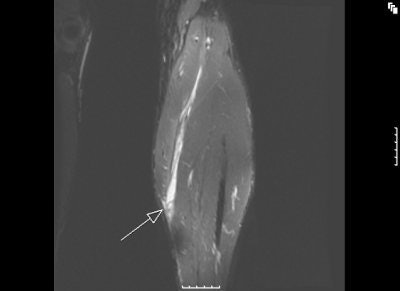

![]() |

MR images of the tennis leg injury sustained by Mintz. Above, a coronal fat-suppressed image through the back of the calf with the arrow pointing to the muscle tear. The hematoma is tracking up the leg. Below, sagittal MR of the whole calf. Arrow points to the muscle tear and the white below it is the gap from the muscle retraction. Images courtesy of Dr. Douglas Mintz.